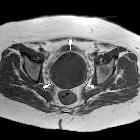

Rhabdomyosarkom des Uterus

Radiographic features

CT

A heterogeneous mass as with ultrasound. Its relationship to other pelvic organs is delineated, in particular, to review for local invasion.

Used to assess for locoregional lymphadenopathy and distant metastatic disease in the lungs, liver and bones.